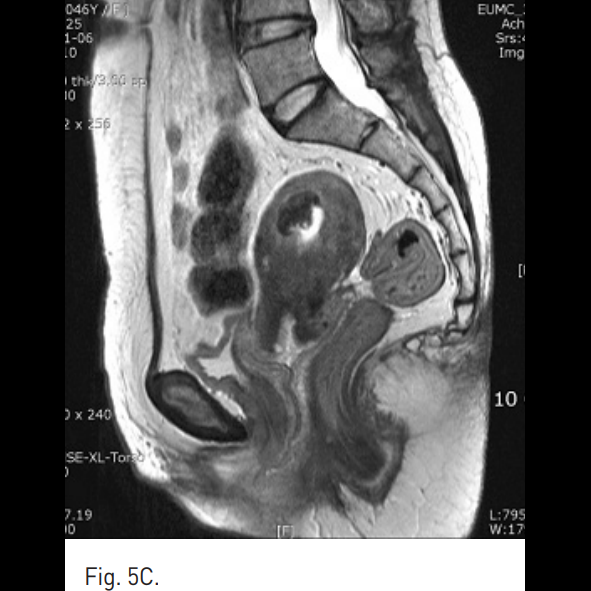

Fig. 5

A-C. One year follow-up T2-weighted transverse (A), coronal (B), sagittal (C) MR images show a small remnant of myoma with low signal intensity.